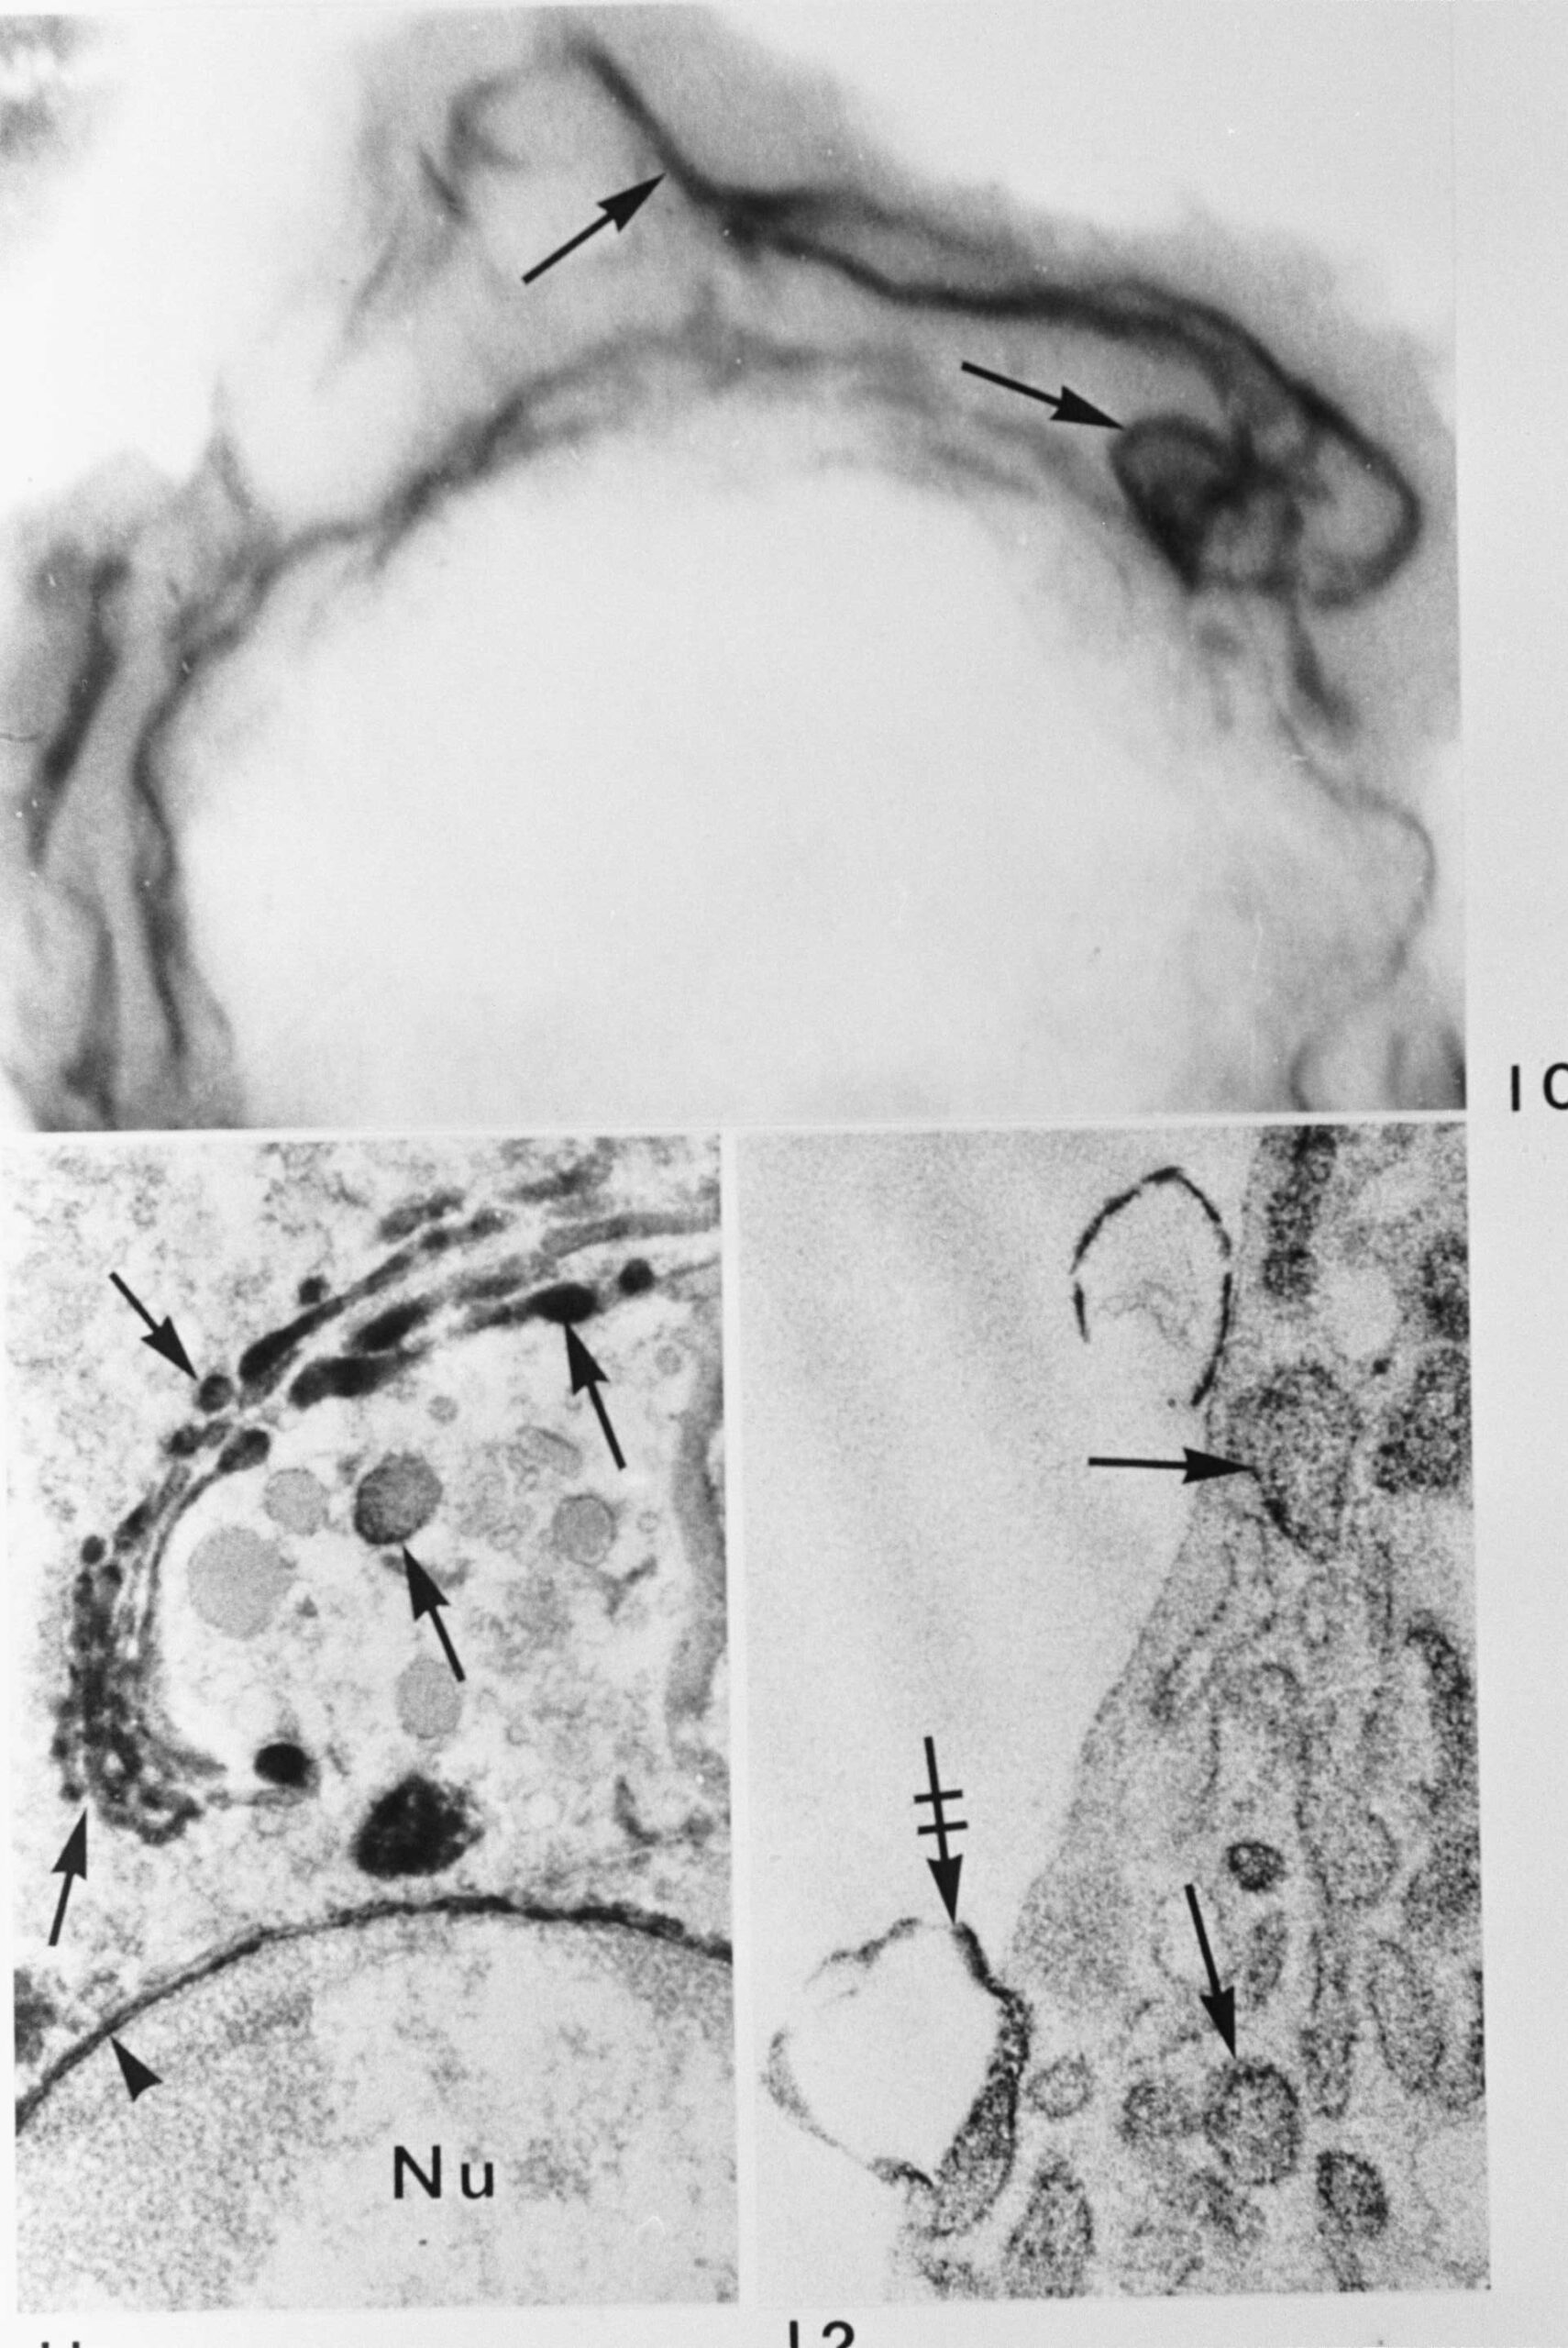

Blast cell as seen in the electron microscope of a 1 µm thick Epon section with interconnected sytem of antibody containing RER lamellae (arrows). Below, left side: Golgi complex of a plasma cell with antibodies in its lamellae and vesicles (arrows), the PNS (arrow head) is also stained. Below, right side: Plasma cell with antibody in RER cisternae (arrows). Note broken RER cistern at cell periphery